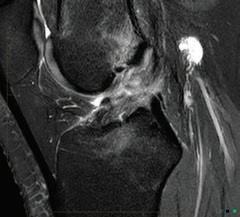

As well as concussion, women athletes are more prone to anterior cruciate ligament (ACL) tears at certain times of their menstrual cycle and Dr Goodman said this was another line of inquiry.

Issuu converts static files into: digital portfolios, online yearbooks, online catalogs, digital photo albums and more. Sign up and create your flipbook.